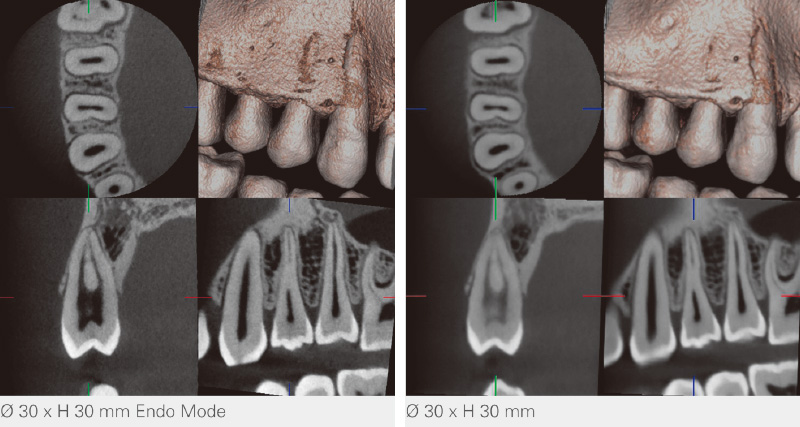

桐村 「X800」には「スタンダードモード」と「ハイレゾリューションモード」という2つの撮影モードが搭載されていました。高い空間分解能と低い画像ノイズは、常に相反するものですが、「スタンダードモード」はそれらのバランスが最も良くなる条件で撮影することができます。一方、「ハイレゾリューションモード」は、ノイズをある程度犠牲にして、高空間分解能に特化したモードです。「X800+」で新たに搭載された「Endoモード」は、根管治療を行う先生方から、高空間分解能でありながら、さらにノイズも低く抑えた小領域撮影を求めるお声をいただき、それを反映させた機能となっています(図2)。

杉原 「3DX」にもデンタルサイズに近づけたφ40×40mmという小照射野の設定があります。今回はそこに立ち戻って、根管治療に必要なサイズをどこまで絞れば良いかというテーマになりました。スカウト機能によりφ30×30mmの小領域でも位置づけが可能であることがわかりました。新搭載の「Endoモード」では、物理フィルタを変更して、根尖組織周辺の描出能向上を図っていますが、φ30x30mmを利用することで、被ばく線量の増加を抑えることができます。導入いただいた先生からは、根管治療だけでなく、経過観察の過程で、部位をできるだけ絞って見たいときに“「Endoモード」はとても重宝する”という評価をいただいています。

新井 φ30×30mmという小照射野になって、X線の照射量はほぼ半減されています。経過観察や根管治療の際には何度かCT撮影が必要なケースがありますが、治療内容によっては1歯だけを狙えば良いので、そうした使い分けができることは、臨床家にとって大きなメリットになると感じています。

![[写真] Endoモード](/academic/dentalmagazine/wp-content/uploads/sites/2/2025/11/195-12_photo02.jpg)

図2 「Endoモード」では、線質を変化させて、軟組織に近い根尖部周辺のコントラスト表現を向上させている。